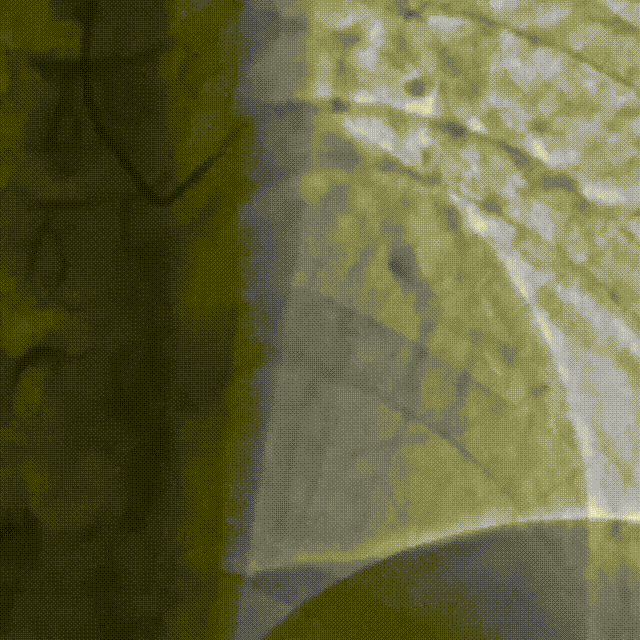

直接使用G3导丝rendezvous,球囊扩张后行IVUS检查确定血管直径及支架落脚点。

D1释放DCB,LAD植入支架后D1血流影响,工作导丝找回后使用球囊扩张并kissing。

造影发现LAD远端病变仍较重,释放DCB。

复查造影并行ivus检查 支架贴壁良好 无累及夹层。